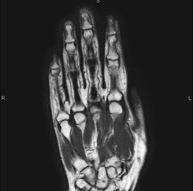

- Hand / finger MRI

Examination to study injuries to tendons, ligaments and small joints. This test is the best way to diagnose frequent capsulitis caused by trauma, osteoarthritis (arthrosis) and tendon tears. It lasts approximately 20 minutes. It is a radiation-free procedure.